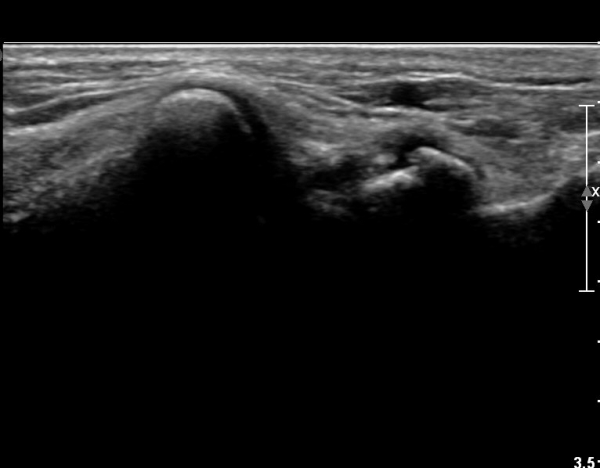

¼Õ¸ñ Ⱦ´Ü¸é°Ë»ç»ó ÁÖ»ó°ñ¿ù»ó°ñ Àδë´Â Á¤»óÀûÀ¸·Î °üÂûµÇ³ª ¿ù»ó°ñ»ï°¢°ñ ÀÎ´ë ºÎÂøºÎ

¿ù»ó°ñ ÇÇÁú°ñÀÇ ºÒ±ÔÄ¢È¿Í »ï°¢°ñ Ç¥ÃþÀÇ °ñÆíÀÌ °üÂûµÈ´Ù(»çÁø 3).

»ï°¢°ñ °ß¿ °ñÀýÀÌ °üÂûµÊ.